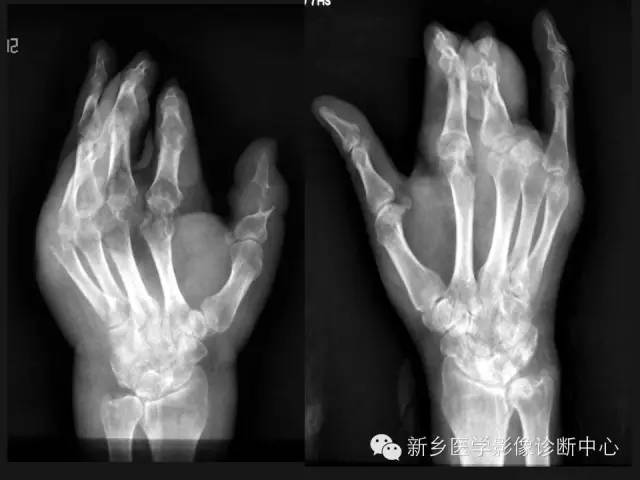

痛风1例X线影像表现